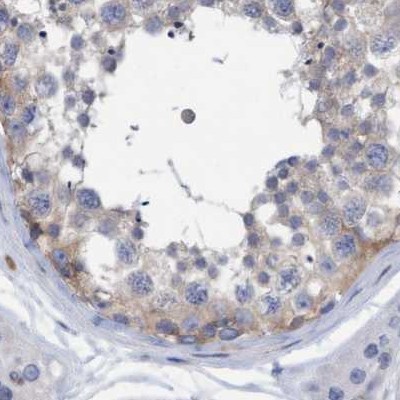

Immunohistochemistry analysis in human lymph node and skeletal muscle tissues using Anti-FNBP1 antibody. Corresponding FNBP1 RNA-seq data are presented for the same tissues.